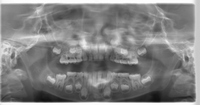

小児のパノラマ写真

今回は口腔外科の分野から小児のパノラマレントゲンについてです。

小児のパノラマレントゲンは目にする機会が少ないので紹介します。

顎の下(オトガイ部)を強打して受診されました。

顎の下をぶつけると顎関節周囲の骨が介達骨折するケースがおおく、

パノラマレントゲンの診査は必須です。

骨折の有無を確認するために撮影しました。

骨折は認められませんでした。

乳歯の下に永久歯が発生するので、

1枚の写真の中に歯がたくさん写ります。

成人のパノラマレントゲンと比べると歯がたくさん写っているのがわかると思います。